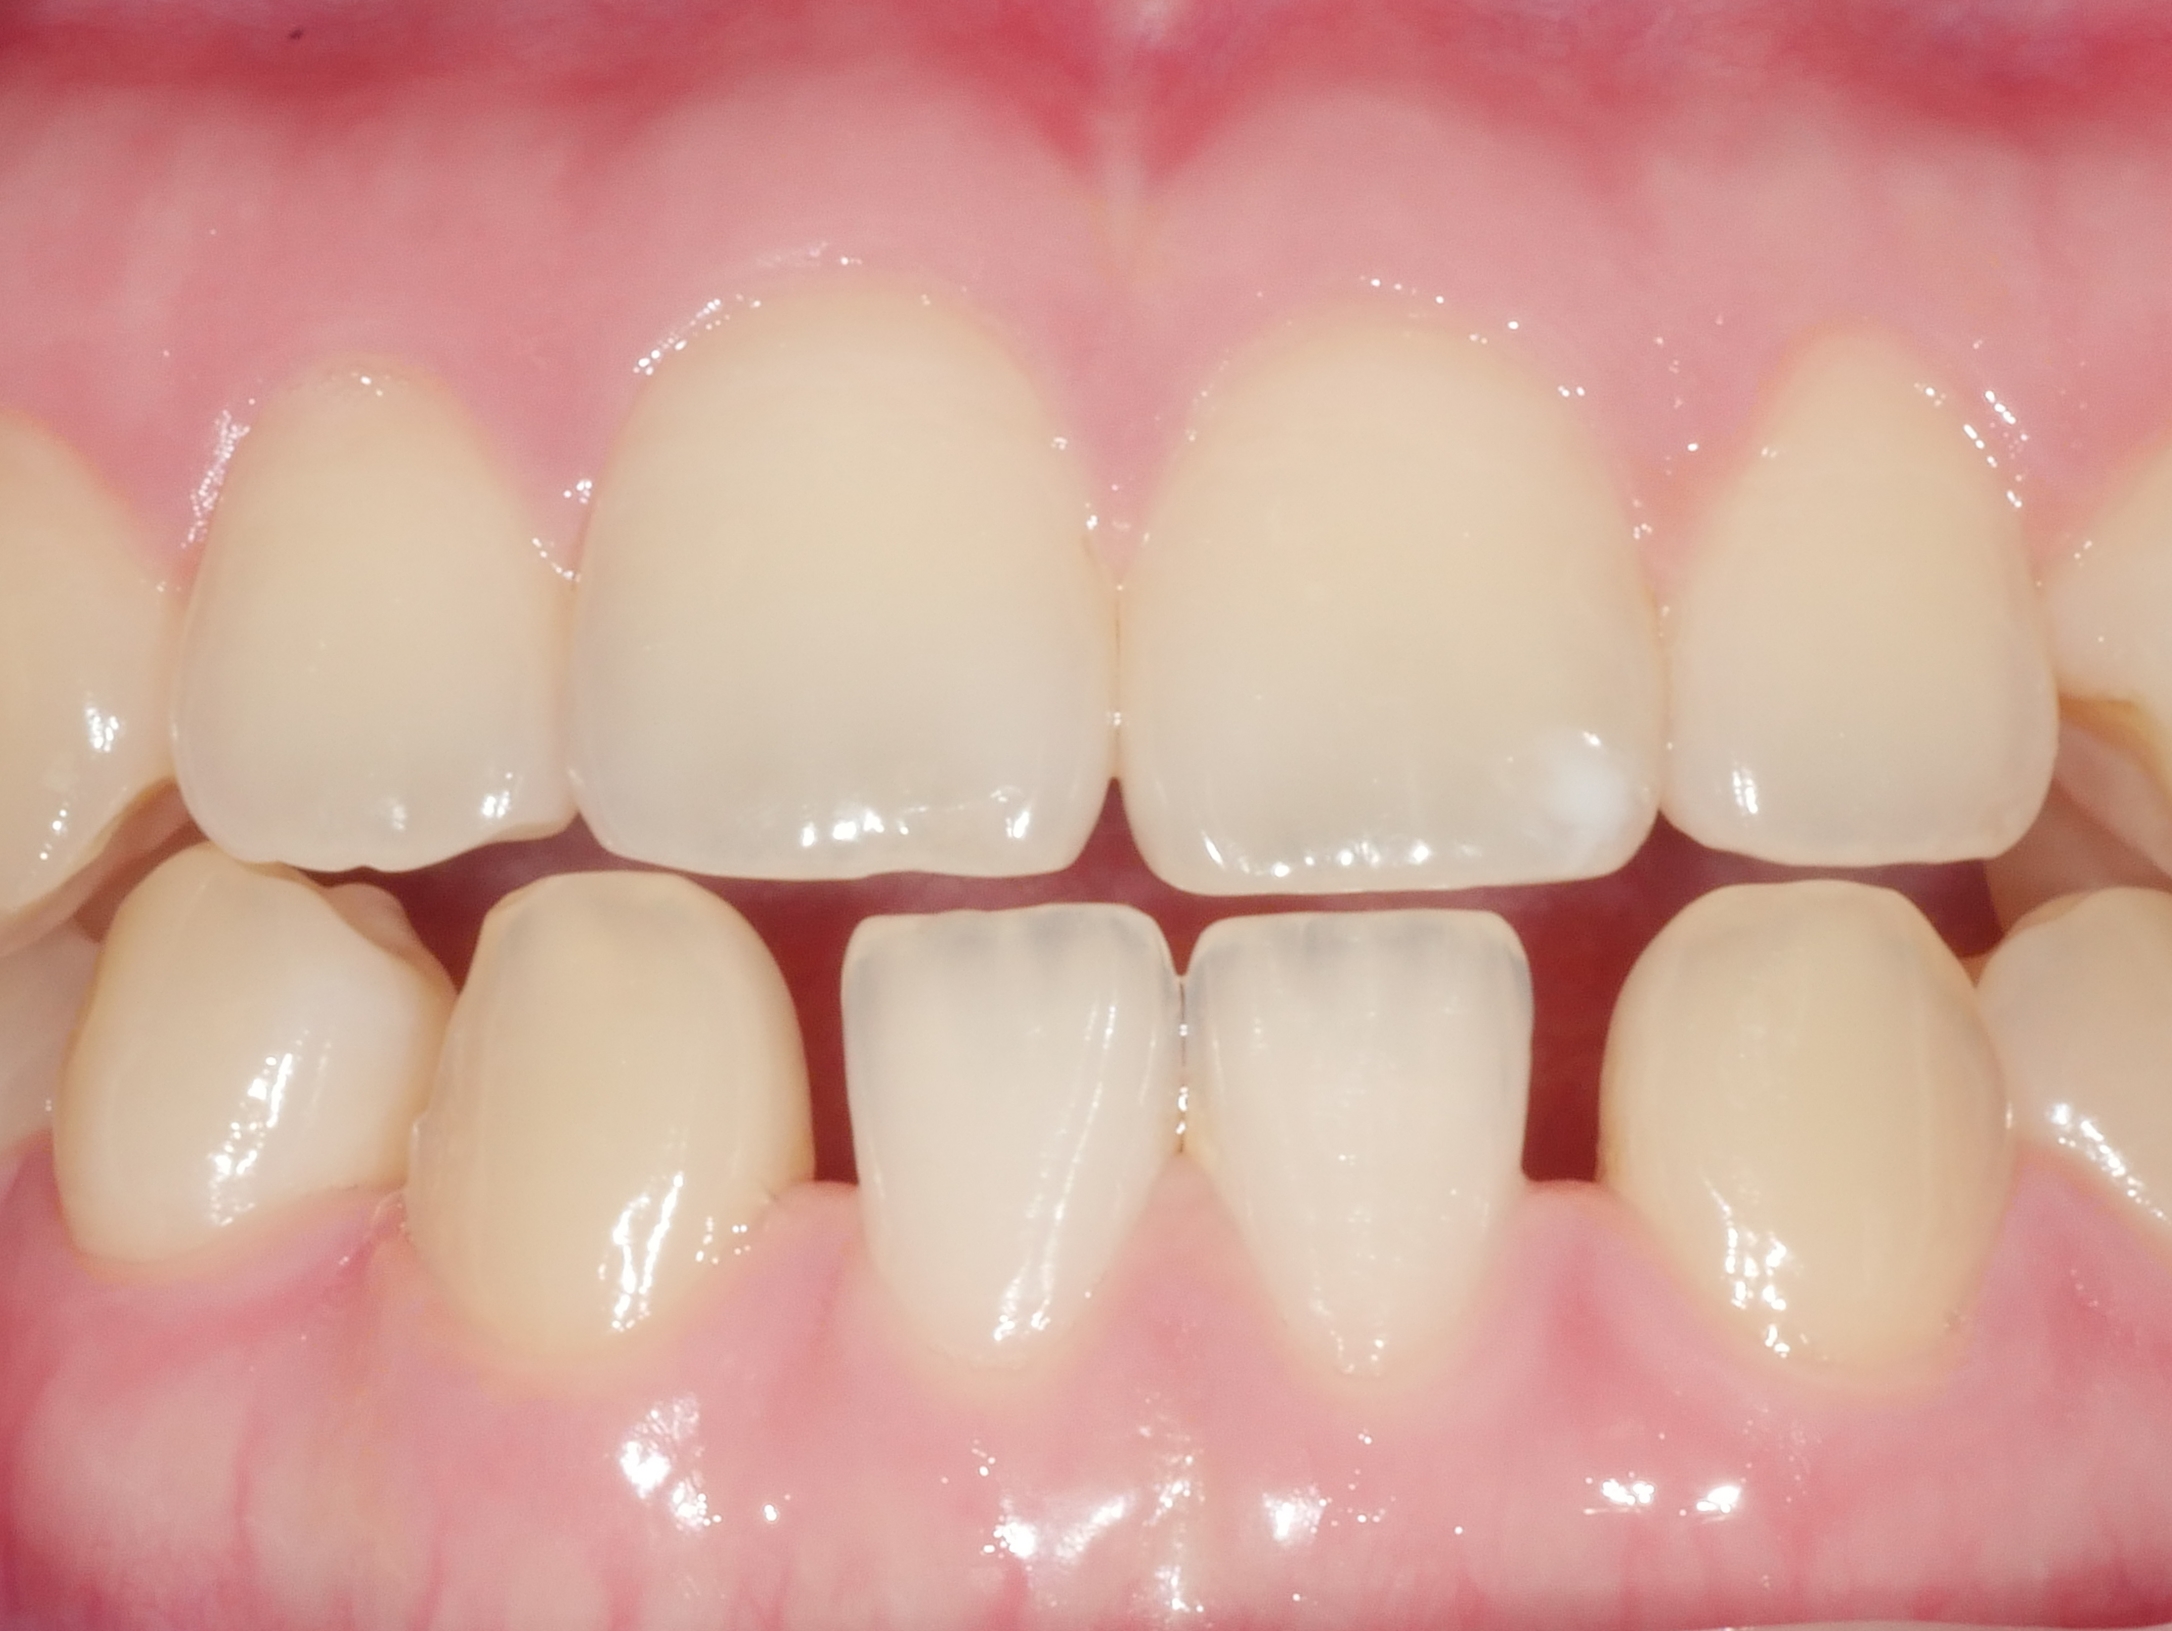

CASE.01 아래 앞니 치아 벌어짐 치료

• 아래 앞니 치아 벌어짐 치료

내원 당일 치아 삭제 없이 레진치료

치료전/후 2024.05.07